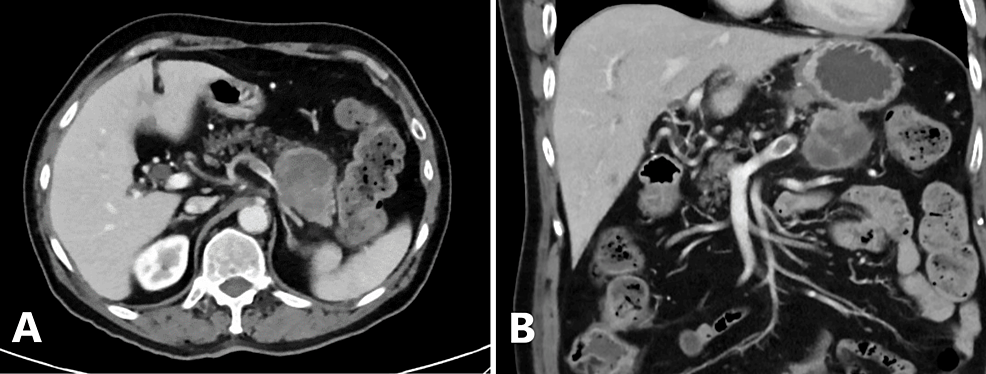

A Rare Case of Rhabdoid Pancreatic Carcinoma: Prolonged Disease-Free Survival Following Upfront Resection and Adjuvant Chemotherapy